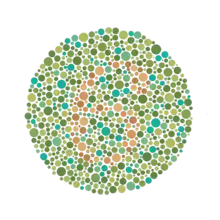

Il permet de détecter toutes les déficiences dichromatiques sauf la tritanopie et la tritanomalie, d’ailleurs très rare. Une planche pseudo-isochromatique est constituée d’une mosaïque de points de couleurs différentes, disposés de façon apparemment aléatoire, au sein duquel apparaît une forme sur un fond. En réalité, les couleurs utilisées sont situées sur des axes de confusion colorés prédéterminés pour mettre en évidence un type de daltonisme précis. On utilise un nombre réduit de teintes. Chacune d’elles apparaît à plusieurs degrés de taille, de saturation et de luminosité. Ces degrés sont identiques pour chacune des couleurs représentées. Un ensemble de points reproduit une forme reconnaissable par l’unité de la teinte, mais, au sein de cette forme, on trouvera plusieurs saturations ou luminosités différentes de façon aléatoire. Le daltonien qui ne verra pas la couleur ne pourra pas non plus déchiffrer la forme par le seul fait d’une homogénéité de saturation ou de luminosité. À l’inverse, il existe des planches dans lesquelles cette homogénéité est utilisée pour faire percevoir des formes à des dichromates alors que les sujets normaux, trompés par des couleurs qui leur paraissent différentes, ne les percevront pas. Dans le daltonisme héréditaire, les lignes de confusion sont nettes et parfaitement déterminées. Cela permet une excellente fiabilité aux planches bien conçues, à la condition que les couleurs soient reproduites à l’impression. En revanche, par construction, une planche pseudo-isochromatique n’est pas adaptable et si l’axe de confusion du dichromate n’est pas rigoureusement celui qui a été prédéterminé, la planche sera jugée défectueuse. Cela se produit le plus souvent dans le cas d’une dyschromatopsie acquise. Chaque groupe de planches (tables) reproduites dans l’annexe (page 27 à 33) doit être interprété différemment.

- Les planches 10 à 13 sont basées sur une confusion bleue verte – orangée. Les individus atteints de la maladie ne perçoivent rien.

Exemples de planches représentant successivement les numéros 12, 6, 2 (visible seulement en cas de déficience rouge-vert) et 42.

Ishihara Planche no 1. Ishihara Planche no 11.

Ishihara Planche no 11. Ishihara Planche no 19.